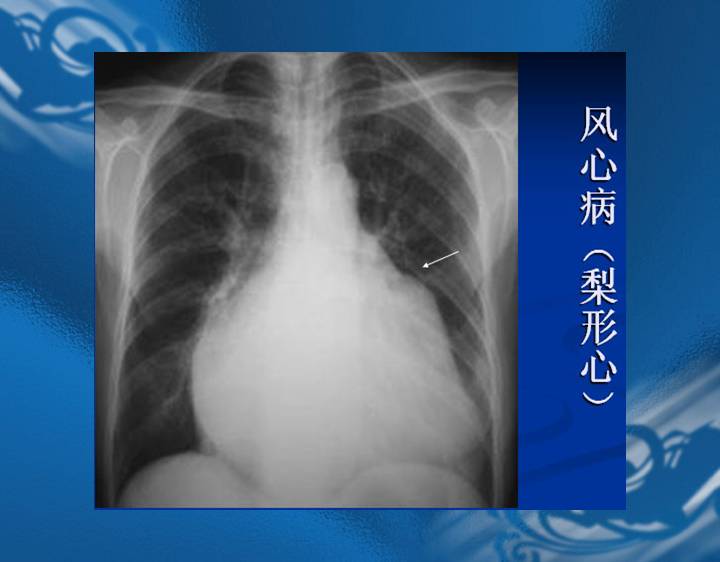

执业医师资格考试“实践技能”影像学辅导资料